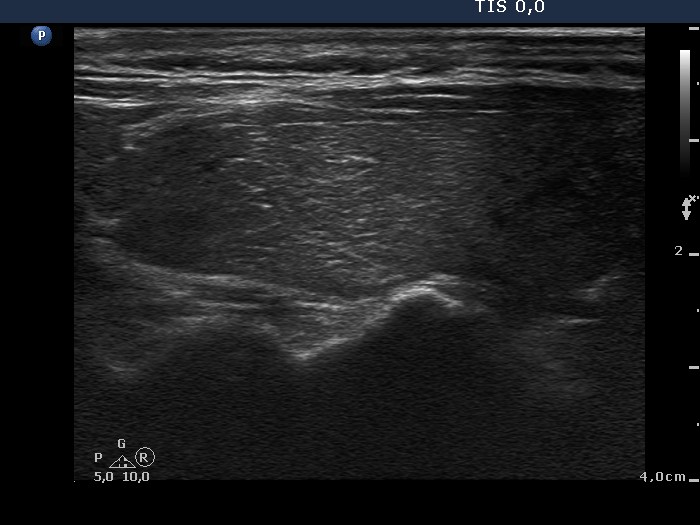

Graves' disease - case 612

Four months after the initial investigation (ultrasonographic picture 2)

Right lobe, longitudinal scan.